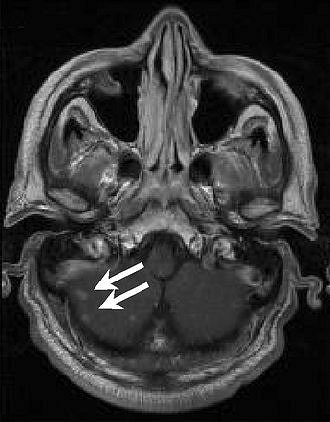

| Above, transverse T1-weighted SE MR image (590/12) in 61-year-old man with metastatic lung cancer after administration of 0.1 mmol/kg of gadopentetate reveals multiple enhancing lesions in right cerebellum and posterior medulla. Below, image acquired with identical parameters as previous image after administration of 0.1 mmol/kg of gadobenate reveals improved contrast enhancement of lesions seen with gadopentetate and unequivocal detection of two additional metastatic lesions (arrows) in right cerebellar hemisphere. |